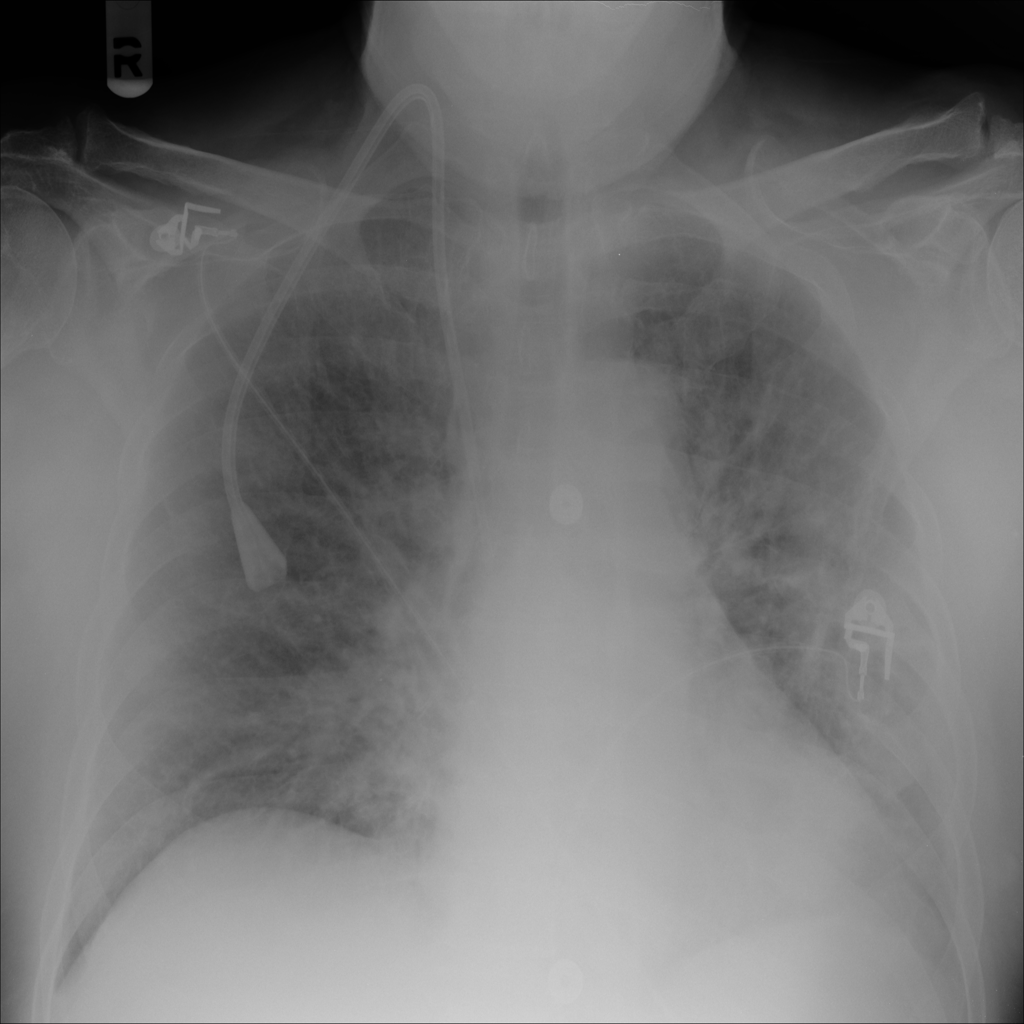

PAT-E828 · IMG-005Edema

PAT-E828 · IMG-005

AP